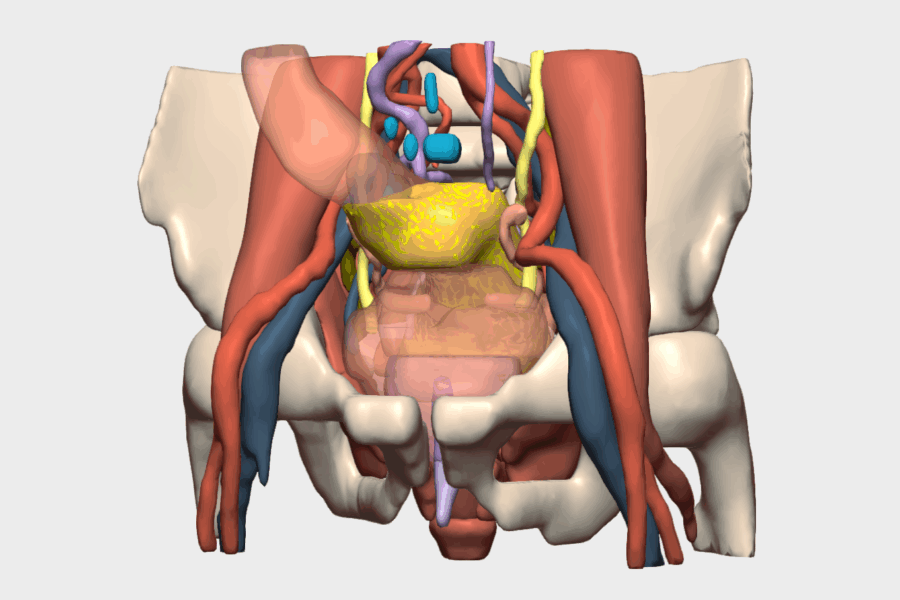

En el protocolo de prehabilitación (GRAMGEA) se detecta déficit leve de Factor VII, valorado por Hematología, indicándose vitamina K preoperatoria. El paciente pesa 80 kg, mide 177 cm (IMC 25) y es clasificado como ASA I. Se administra bolo de hierro IV (1500 mg) y se indican ejercicios de fisioterapia respiratoria. En quirófano se dispone de un modelo 3D virtual personalizado, basado en las pruebas de imagen del paciente, visible y navegable durante toda la intervención, lo que permite una cirugía dirigida, precisa y personalizada. Se localiza la tumoración en el ángulo esplénico, con gran induración, neovascularización e invaginación colocólica, hallazgos correlacionados con el modelo 3D. Se identifica la vena mesentérica 2 inferior (VMI) y se realiza disección mesocólica respetando cola de páncreas, bazo y fascia de Toldt izquierda.

Gracias a la reconstrucción 3D, se identifican dos arterias cólicas izquierdas procedentes de la Aorta, además del tronco de la cólica izquierda de la Arteria Mesenterica Inferior (AMI) permitiendo una ligadura vascular selectiva, respetando la arteria mesentérica inferior y la cólica izquierda más distal que no interesa la tumoración ni el margen de resección de seguridad, optimizando de esa manera la colectomía segmentaria del ángulo esplénico. Se realiza además sección de la rama izquierda de la cólica media.

La reconstrucción 3D fue especialmente relevante en la identificación y comprensión de la anatomía vascular mesentérica, donde se objetivó la presencia de dos arterias cólicas izquierdas, una variante anatómica con impacto directo en la estrategia quirúrgica.

Asimismo, permitió anticipar la localización exacta del tumor en el ángulo esplénico, su relación con la invaginación colocólica y con estructuras críticas como el páncreas y el bazo, reduciendo la incertidumbre intraoperatoria y aumentando la seguridad del procedimiento

El modelo 3D de CELLA permitió una visualización interactiva y navegable en tiempo real, con segmentación detallada de vasos, colon, mesocolon y órganos adyacentes. La posibilidad de rotar, aislar estructuras y correlacionar la imagen virtual con la anatomía real durante la cirugía fue clave para la identificación vascular precisa y la planificación de una resección segura. Esta funcionalidad aportó un valor diferencial al facilitar una cirugía más predecible, personalizada y eficiente, con mínima pérdida hemática y excelente evolución postoperatoria.